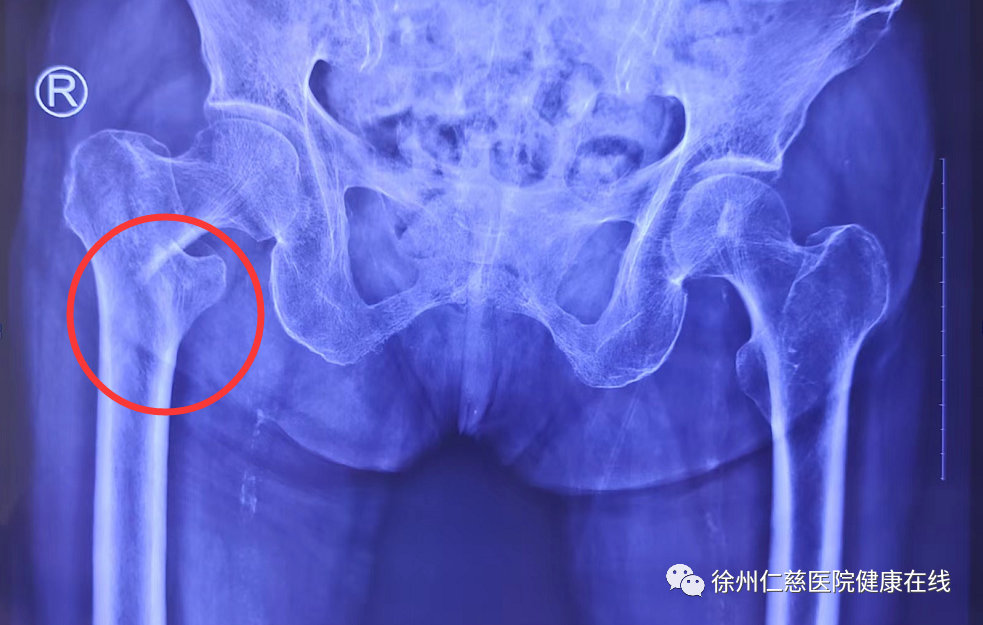

意外跌倒,百岁老人右股骨粗隆间骨折

家人们将张奶奶带到徐州仁慈医院就诊,关节外科医生为张奶奶进行了仔细检查,通过 X 线片显示,张奶奶右股骨粗隆间骨折。